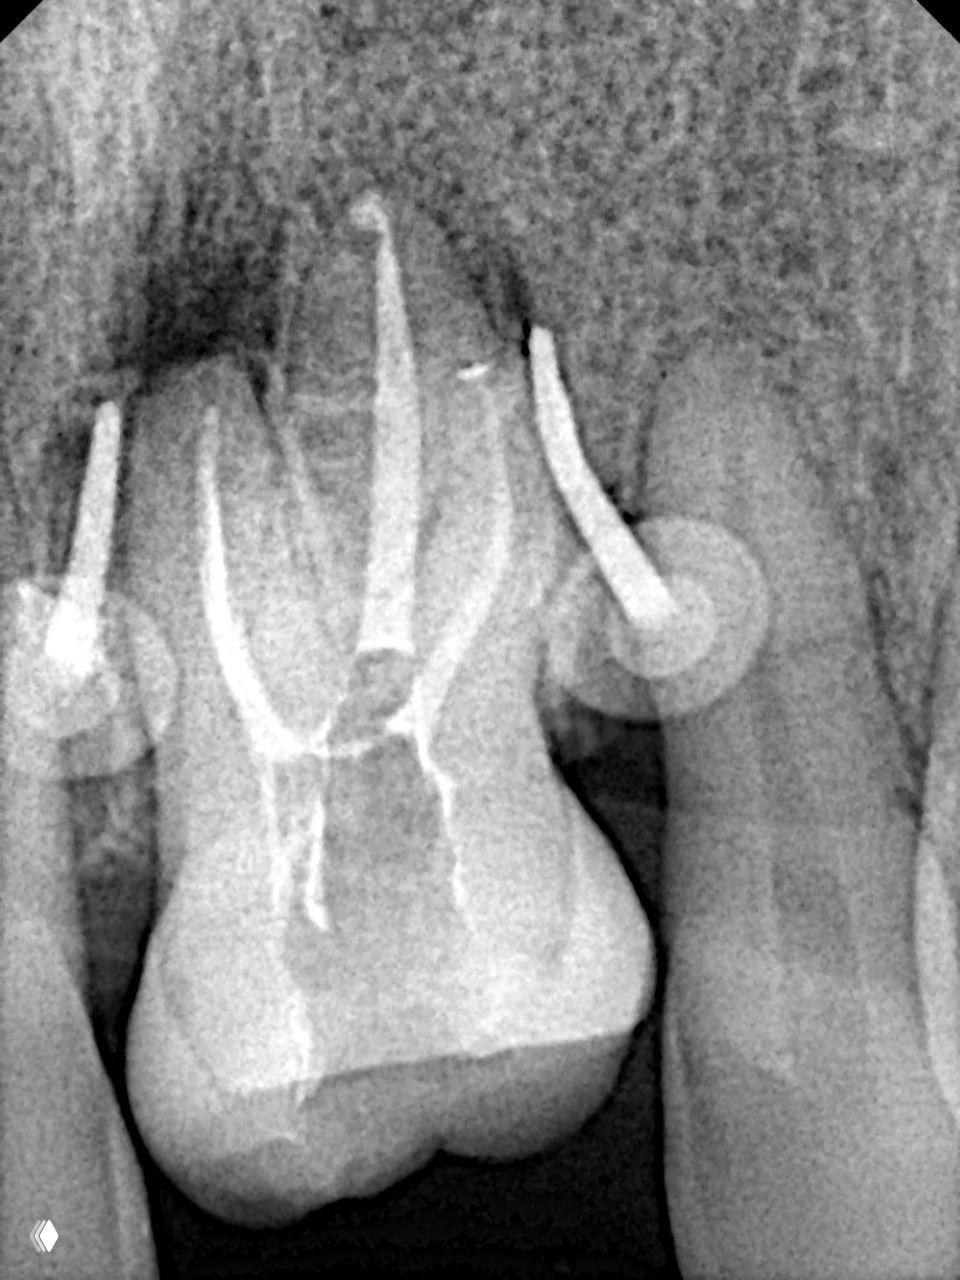

- Как сформировать доступ и найти все устья

- Какие файлы брать и в какой последовательности

- Как проводить ирригацию так, чтобы провести максимальную дезинфекцию корневых каналов

- Как пломбировать каналы с предсказуемым результатом